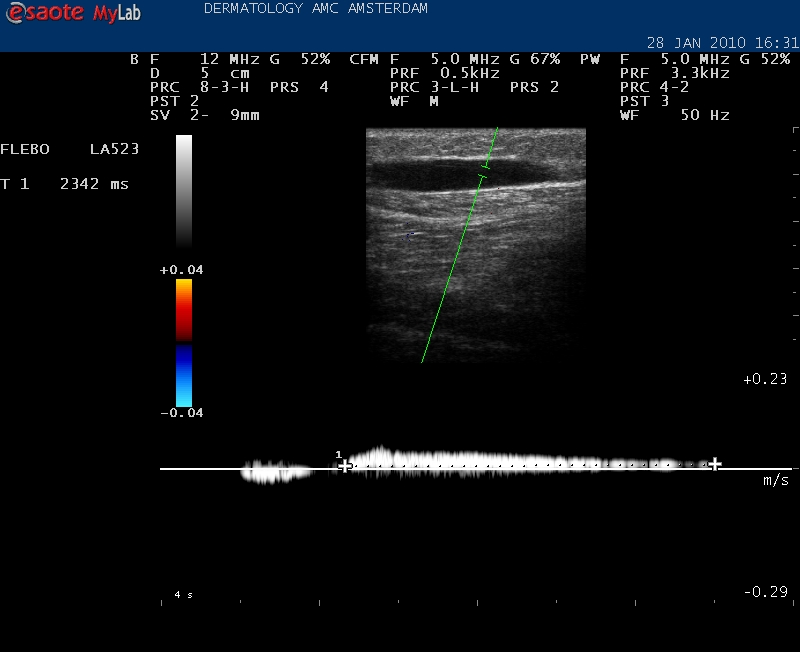

| Met de duplex kan ook de reflux over het vat worden gemeten. |